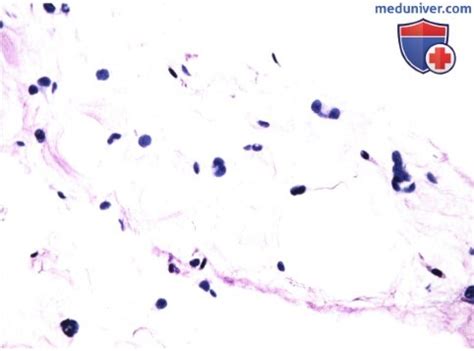

Липома. Липоматоз. Липобластома. Гибернома.

Липома патанатомия